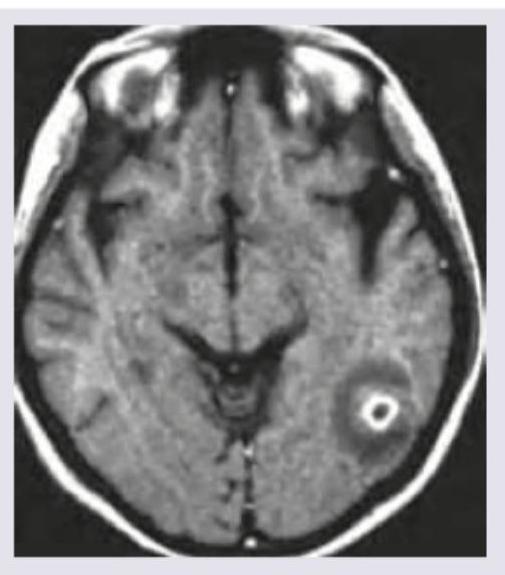

A 30-year-old patient has suffered from multiple episodes of GTCS for the last one week. MRI was performed. All are true about the condition except:

Explanation: ***Steroids must be given in the racemose form*** - The **racemose form** of neurocysticercosis (NCC) specifically refers to cysticerci growing in clusters within the subarachnoid space, often **without a scolex, and can be difficult to treat due to their inflammatory nature and location. Systemic steroids** would likely be indicated for significant cerebral edema and inflammation, but they are not *mandatory* and their efficacy in directly improving the racemose form itself is limited or unproven, nor are they a specific treatment for the racemose form, but rather used to manage inflammation. - The image provided shows a solitary, enhancing lesion, more consistent with a parenchymal cyst at the **colloidal vesicular stage**, not the racemose form. *MRI shows colloidal stage of NCC* - The MRI image displays a **ring-enhancing lesion with perifocal edema**, which is characteristic of the **colloidal vesicular stage** of neurocysticercosis. In this stage, the larva starts to degenerate, triggering a significant inflammatory response. - The central high signal intensity represents the degenerating scolex or colloidal fluid, and the surrounding low signal is indicative of extensive vasogenic edema, which can lead to seizures like the GTCS described. *CSF eosinophilia* - **CSF eosinophilia** (presence of eosinophils in cerebrospinal fluid) is a common finding in neurocysticercosis, especially when the cysts are located in the subarachnoid space or ventricles, or when there is significant inflammation. - The immune response against the parasite often involves eosinophils, making their presence in the CSF a supportive diagnostic indicator. *Enzyme-linked immune-electrotransfer blot assay is more sensitive than CSF ELISA* - The **Enzyme-linked immune-electrotransfer blot (EITB) assay** (Western blot) is considered the **gold standard** for serodiagnosis of neurocysticercosis due to its high **sensitivity (nearly 100%) and specificity (nearly 100%)**, particularly for patients with active lesions and viable cysts. - While **CSF ELISA** can detect antibodies, it generally has **lower sensitivity** compared to EITB, especially when only a single brain lesion is present, or in the very early or late calcified stages of the disease.